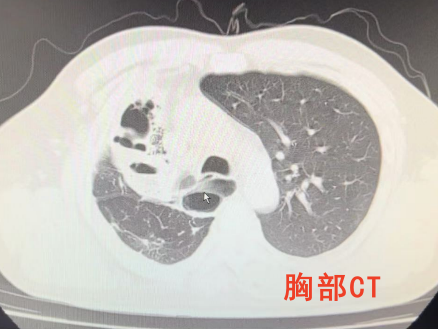

患者入院后完善胸CT检查,提示右上肺毁损、支气管扩张合并感染,食管扩张,气管可疑瘘口。气管镜检查见隆突上方约2cm处膜部见一横形瘘口;胃镜检查见食管上段原吻合口瘢痕下方一圆形瘘口。